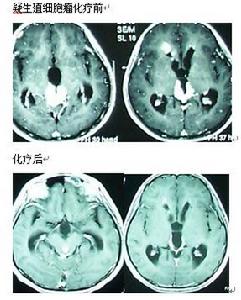

生殖細胞瘤的高發地日本於1983年首先提出實驗性放療的概念,並運用至今。專家提醒:要確認腫瘤或占位的病理性質只有手術切除或者活檢兩種方法.試驗性放療是間接判斷生殖細胞腫瘤(GCTs)/占位具體性質的一種簡便.實用,較安全的方法,多數情況下可區分germinoma和NG-GCTs或其它性質占位,但通過此方法得出的初步診斷,是個人的主觀判斷,只有經過長期實踐,積累了豐富臨床經驗的醫生才能勝任,才能最大限度的減少誤診誤治的可能.見圖。

臨床疑NG-MGCTs且AFP陽性患者可採用PEB,VIP等方案,化療目的:判斷腫瘤對化療的敏感性,決定下一步治療方案。見圖。松果體區生殖細胞瘤